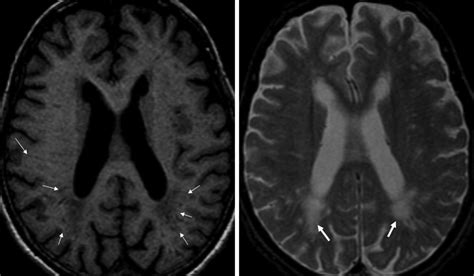

Diagnosing White Matter Disease typically relies on advanced imaging techniques rather than just clinical observation. Physicians look for specific patterns of damage that distinguish this condition from others like Alzheimer’s or stroke.

MRI (Magnetic Resonance Imaging) The gold standard for identifying white matter hyperintensities (bright spots on the scan indicating damage).